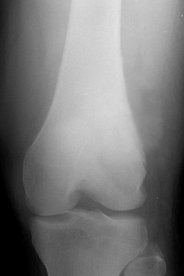

골육종을 의사가 의심하게 되는 것은 단순 방사선 촬영(X-ray)에서 이상 소견이 보일 경우이다. 이렇게 골육종이 의심될 경우 골 종양을 전문으로 하는 정형외과 전문의에게 의뢰하게 된다. 골육종의 확실한 진단은 조직 검사(조직의 일부를 떼어 현미경으로 관찰하는 것)를 하여 이루어지게 된다.